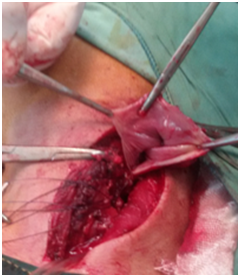

All six patients were symptomatic Four of patients were male. Age of patients was 65 to 80years. Four of patients came with dysphasia aspiration, halitosis, and malnutrition and regurgitation, one of this patient present three period with aspiration pneumonia and hospital admission. One of patients underwent endoscopic diverticulotomy and 24 hour after this procedure present with odynophagia, fever and neck subcutaneous emphysema With B-swallow perforation of diverticula was demonstrated, this patient underwent neck exploration and diverticulectomy and drainage. Diagnostic tools of five cases was B-swallow and esophagoscopy (Figures 1-5). One came with food marital retention and pain and neck mass tender mass. One patients referred with erithem, redness and criptation of neck with diagnosis of diverticulitis (Figures 6 & 7). Two cases underwent flexible endoscopic diverticulotomy, one failed and another ones complicated with perforation. The most common surgical approaches was diverticulectomy and myotomy in four patients (Figures 8 & 9). Food debris was present in one patient (Figure 10). Two of patients underwent diverticulectomy without myotomy. Complication and mortalities were zero. In two years flow-up, Outcome was good.

Figure 8 Show swallow pouch of huge Zenker's diverticulum after opening.

Figure 9 Show swallow pouch of huge Zenker's diverticulum after opening.